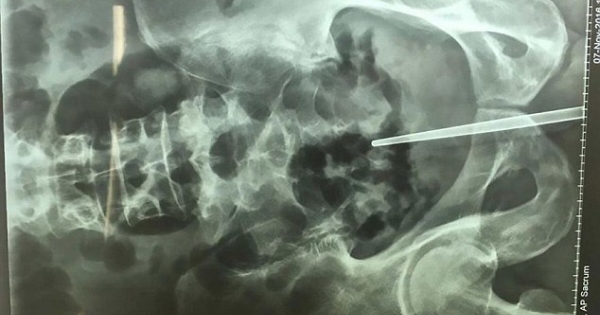

不久前,大陆杭州一名男子到医院就诊,称自己这几天肚子痛,小便困难。医生为他照X光,本来想看看他的泌尿系统是否病变,没想到竟然看到了难以置信的一幕。一根约18cm长的不鏽钢筷子…